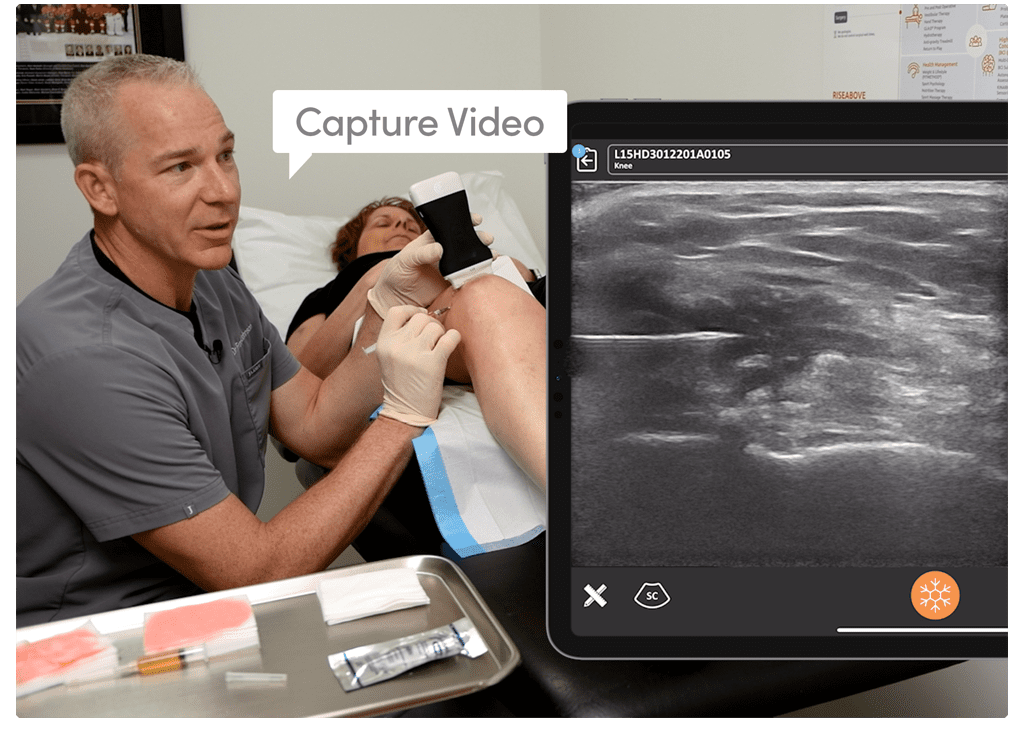

I feel more confident with my ultrasound exams since I’ve started using OB AI. I love how the AI makes the app light up when things are perfectly lined up – I can see this really helping both seasoned clinicians and those who are starting their ultrasound journey.